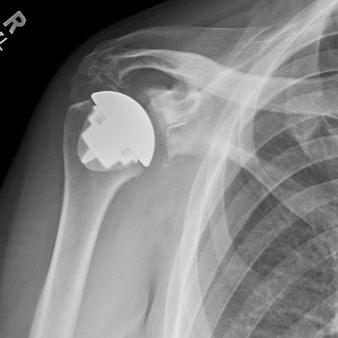

Anatomic Stemless